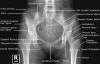

2. Inlet View

Demonstrates: egg-shaped appearance of pelvic ring, sacral promontory should overlap the anterior cortex of the body of the first sacral vertebra

Helpful for: Acetabular fx, Pelvic ring injury, sacral fracture

Position: Supine Center cassette midway between ASIS and pubic symphysis.

Beam directed 40° cephalad

3. Outlet View

Demonstrates: Wedge-shaped appearance of the sacrum when viewed from the front, iliac wings, pubic rami. Top of the symphysis pubis should be at the level of the second sacral body.

Position: Supine. Center cassette midway between ASIS and pubic symphysis.

Beam directed 45° caudad